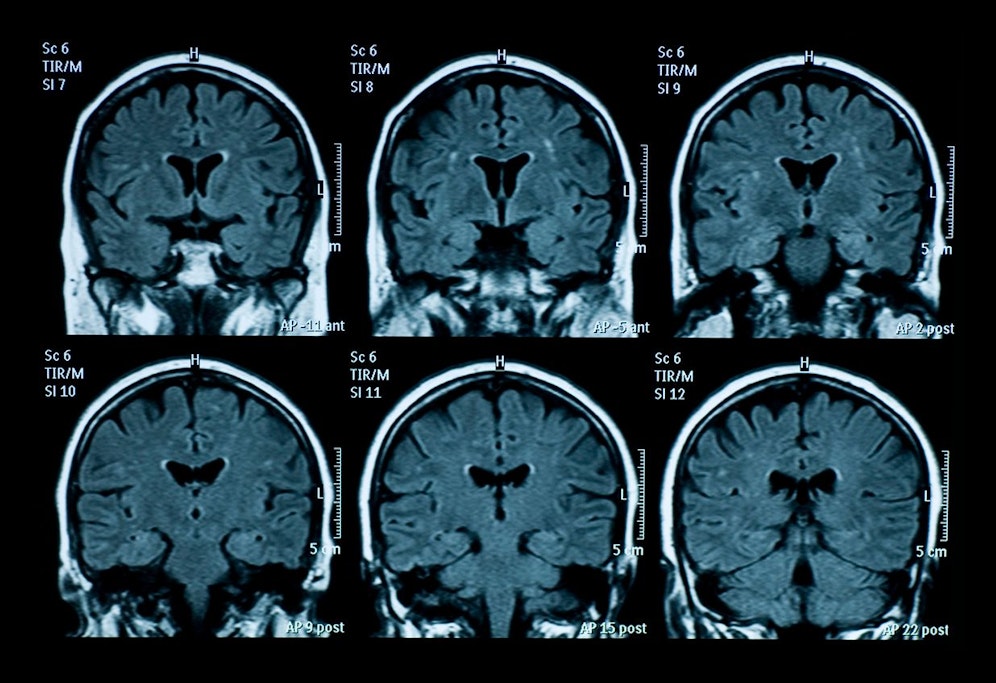

Der New Yorker wurde eingeliefert, nachdem er nach einem Sturz nicht gehen konnte und halluzinierte. Zudem hatte er unwillkürliche Zuckungen. "Der Mann unterzog sich einem MRT des Gehirns, aber die Ergebnisse waren nicht aufschlussreich. Ein Liquorprotein 14-3-3-Test fiel positiv aus, was den Hinweis auf das Vorliegen einer Prionenkrankheit gab. Protein 14-3-3 ist ein Eiweißstoff, der in der Gehirn-Rückenmark-Flüssigkeit (Liquor) bestimmt werden kann. Bei der Einlieferung wurde festgestellt, dass der Patient COVID-19-positiv war, "aber abgesehen von den typischen COVID-Atemmanifestationen keine Symptome aufwies", so die Fallstudie. Jedoch verschlechterte sich sein  Zustand weiter.